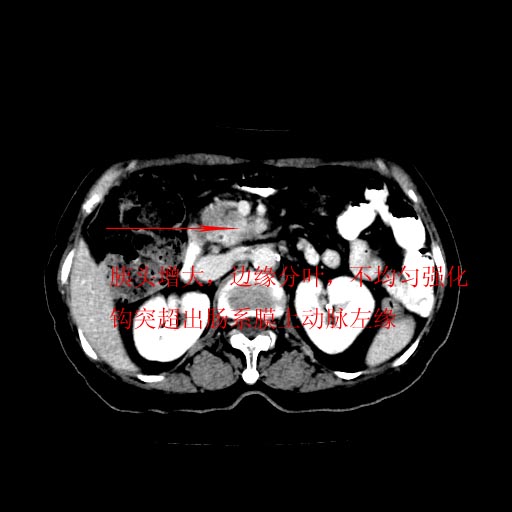

女,74岁,上腹部不适、腹胀两月余,黄染四天。请大家看看肿块周围血管情况。

肝内外胆管增粗,梗阻点位于胰头部,胰头增大,轻度不均性强化(较正常胰腺强化低,胰体尾呈退化';羽毛状';),孝虑为胰头ca.

肝内外胆管和胰管扩张,胆囊明显增大,胰头外形增大,无强化,考虑:胰头癌伴肝内外胆管、胆囊扩张积液。

肝内外胆管增粗,梗阻点位于胰头部,胰头增大不均性明显强化,胰体尾部萎缩,胰管显影,虑为胰头ca.

肝内外胆管及胆囊扩张,胰管扩张,但“双管征”不明显,胆总管下段内见软组织有强化影,肠系膜上静脉推移不是很明显,考虑胆总管下段癌可能大。

胆囊胆总管扩张,胰头与十二指肠间似有一软组织密度灶,胰头增强不均,1壶腹癌,2胰头癌